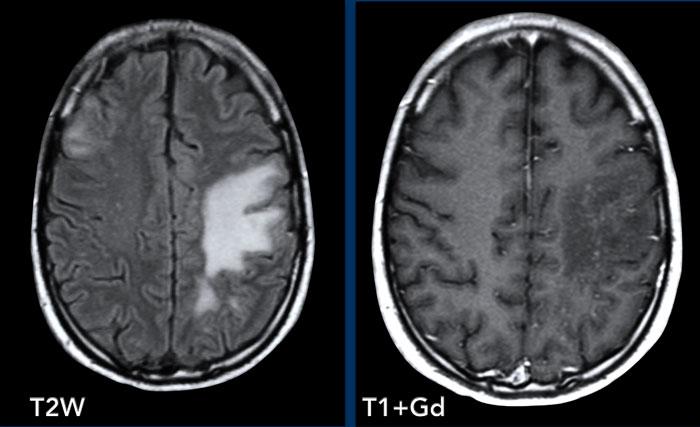

Các hình ảnh này của bệnh nhân 55 tuổi, nhập viện với các triệu chứng đau đầu và mất ngôn ngữ.

Hãy quan sát các hình ảnh trước rồi tiếp tục đọc.

Hình ảnh

Ghi nhận một tổn thương vùng trán-thái dương trái, tăng tín hiệu trên chuỗi xung T2W, với vòng viền ngấm thuốc dày và không đều.

Tổn thương lan dọc theo và xâm lấn vào chất trắng theo hướng bó móc và các sợi chữ U.

Trung tâm tổn thương không có hạn chế khuếch tán và không ngấm thuốc, nhiều khả năng là vùng hoại tử.

Chẩn đoán có khả năng nhất là GBM (u nguyên bào thần kinh đệm).